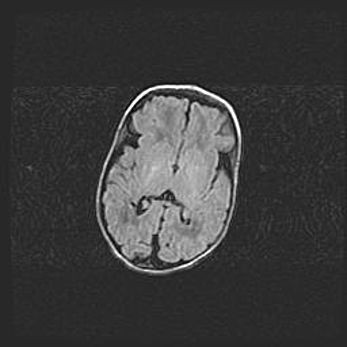

Открытая гидроцефалия.

Возраст: 9 месяцев 12 дней

Вес: 6800 г

Пол: мужской

Окружность головы: 41,5 см

Срок гестации: 28 недель

Гидроцефалия головного мозга у новорожденных имеет характерный признак: опережающий рост окружности головы приводит к визуально хорошо определяемой гидроцефальной форме сильно увеличенного в объёме черепа. Детские неврологи определяют следующие симптомы гидроцефалии у грудничков: выбухающий напряжённый родничок, частое запрокидывание головы, смещение глазных яблок к низу.